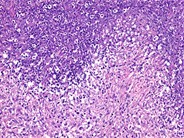

Neutrophil-rich areas within the coagulative necrosis form microabscesses. H&E stain. 200x Magnification.